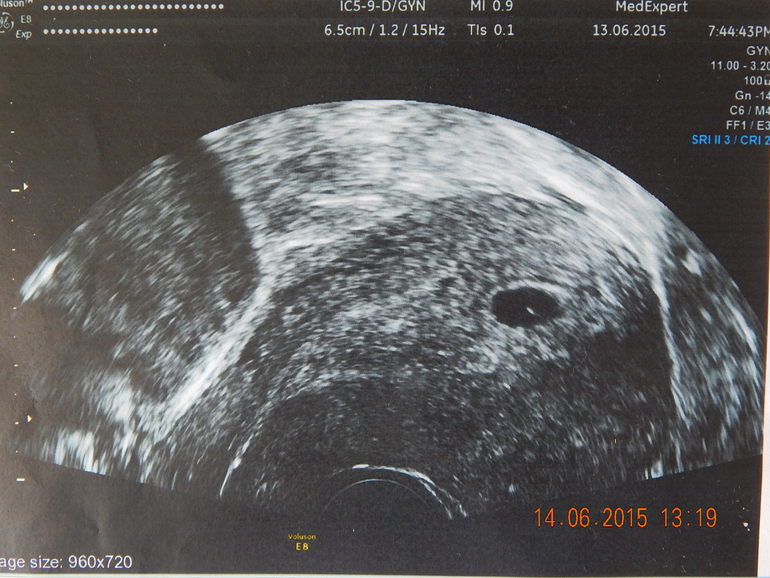

Разница между этими узи 2 недели. Фото под кат

Это первое

А это спустя две недели, на том же аппарате:

вообще не понятно... отслойки по снимку нет, гематомы нет. а вот эмбрион слишком эхогенный, странно... давай подождем недельку опять! лишь бы росло! и хгч точно надо пару раз сдать

А что значит эхогенный эмбрион? Вот и узистка говорит по узи все хорошо, но если не знать, когда были М!

Он как бы очень плотный... Вот бы в динамике глянуть..

Повторюсь,что даже динамики роста пя нет. В 9 недель акушерских уже человечек ручками машет.....я думаю увы